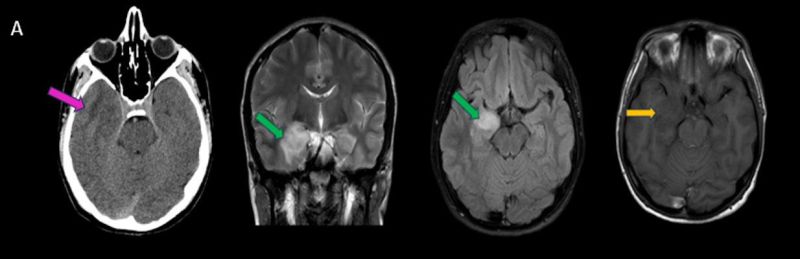

- A) Sağ temporal lob anteromedialinde silik sınırlı BT’de hipodens (ok), MRG’de T2AG ve FLAIR hiperintens (oklar), T1AG izo-hipointens (ok) sinyal özelliğinde ekspansil kitlesel lezyon izlenmektedir.

- B) Lezyon difüzyon görüntüde izo-hiperintens, ADC haritalamada hafif hiperintens izlenmiş olup (oklar) diffüzyon kısıtlılığı göstermemektedir. Lezyonun anterior kesiminde kontrastlı serilerde yamalı kontrast tutulumları (oklar) mevcuttur. MR spektroskopide lezyon düzeyinden elde olunan multivoksel görüntülerde kolin pikinde artış ve NAA da azalma (oklar) dikkati çekmektedir. Kolin/kreatinin oranı 1.76 olarak ölçülmüştür.

- BT: Spesifik olmayan kitle bulgularıdır. İzo-hipodens olarak izlenir. Kitle %35 oranında kalsifikasyon gösterebilir. Olgumuzda kalsifikasyon izlenmemiştir. Kemik remodelasyonu da eşlik edebilir.

- MRG: T1A serilerde solid komponent izo-hipointens, T2A serilerde genellikle hiperintens sinyalde görülür. Peritümöral T2/FLAIR hiperintens kitle ödemi oldukça nadirdir. T1 C+ görüntülerde solid komponentte değişken oranda kontrastlanma ,T2*(SWI) serilerde eğer kalsifikasyon eşlik etmekteyse buna bağlı blooming artefaktları görülebilir.